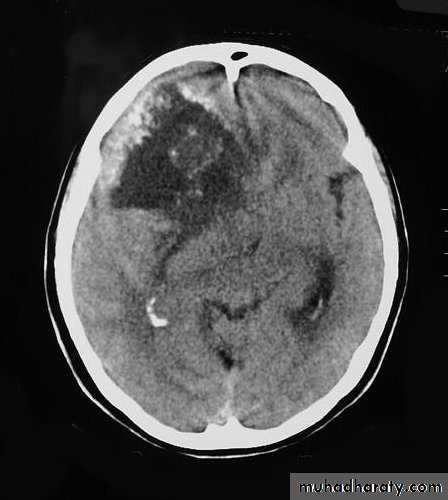

Malignant GliomaPre contrast CT

Neuro surgery

Malignant Glioma Post contrast CT